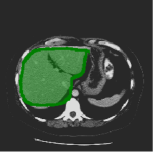

Consider a three-dimensional object within a volume. It is straightforward to produce a 3D bounding box of the object by finding its extreme points in the three coordinate axes. While this 3D bounding box will be tight in the 3D sense, its rectangular cross-sections will not, in general, remain tight with respect to the planar cross-sections of the volume. Fig. 1 illustrates such a case for the task of liver segmentation in a CT volume. In the Experiments section we show that the success of existing 2D weakly-supervised segmentation methods relies on the bounding boxes being tight and therefore the tightness of the individual 2D bounding boxes should be corrected before training and applying a segmentation CNN.

(a)

(b)

(c)

(d)

The global bounding box tightness prior mentioned above assumes that each of side of the box is sufficiently close to the target region. This means that for any region shape, each vertical or horizontal line inside the bounding box will cross at least one pixel belonging to the target region. This condition does not hold when the provided annotation comes as a 3D bounding box which is represented as a series of per-slice non-tight 2D bounding boxes. In this case, there will exist vertical or horizontal lines shown as stripes in Fig. 1 (d), that will lie outside of the actual object boundary. In the Experiments section we demonstrate the poor performance of the weakly-supervised approach from [5] when the user-provided bounding box is much wider than the true object of interest.